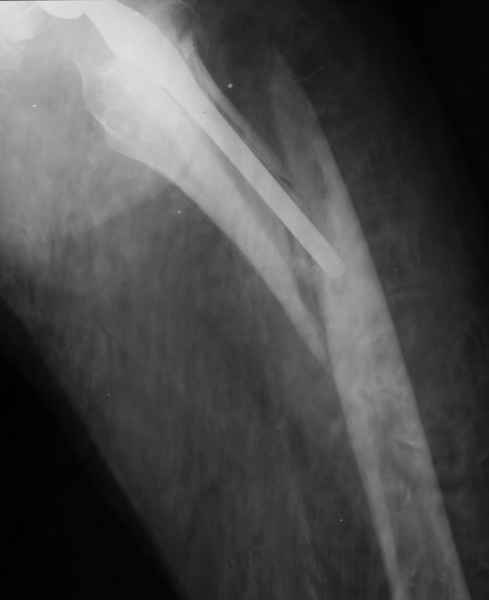

2. Применение ножки дистальной фиксации, мы отдаем предпочтение ножке Вагнера с фиксацией проксимального отдела на ножке. Более травматичное вмешательство, но при стабильной фиксации ножки реабилитация идет в обычном режиме.

Хочется показать два подобных случая, П-ка З. 72 лет и п-т Г. 80 лет. Сразу принимаю замечание, что это были ножки цементной фиксации, просто под руками не было бесцементника.